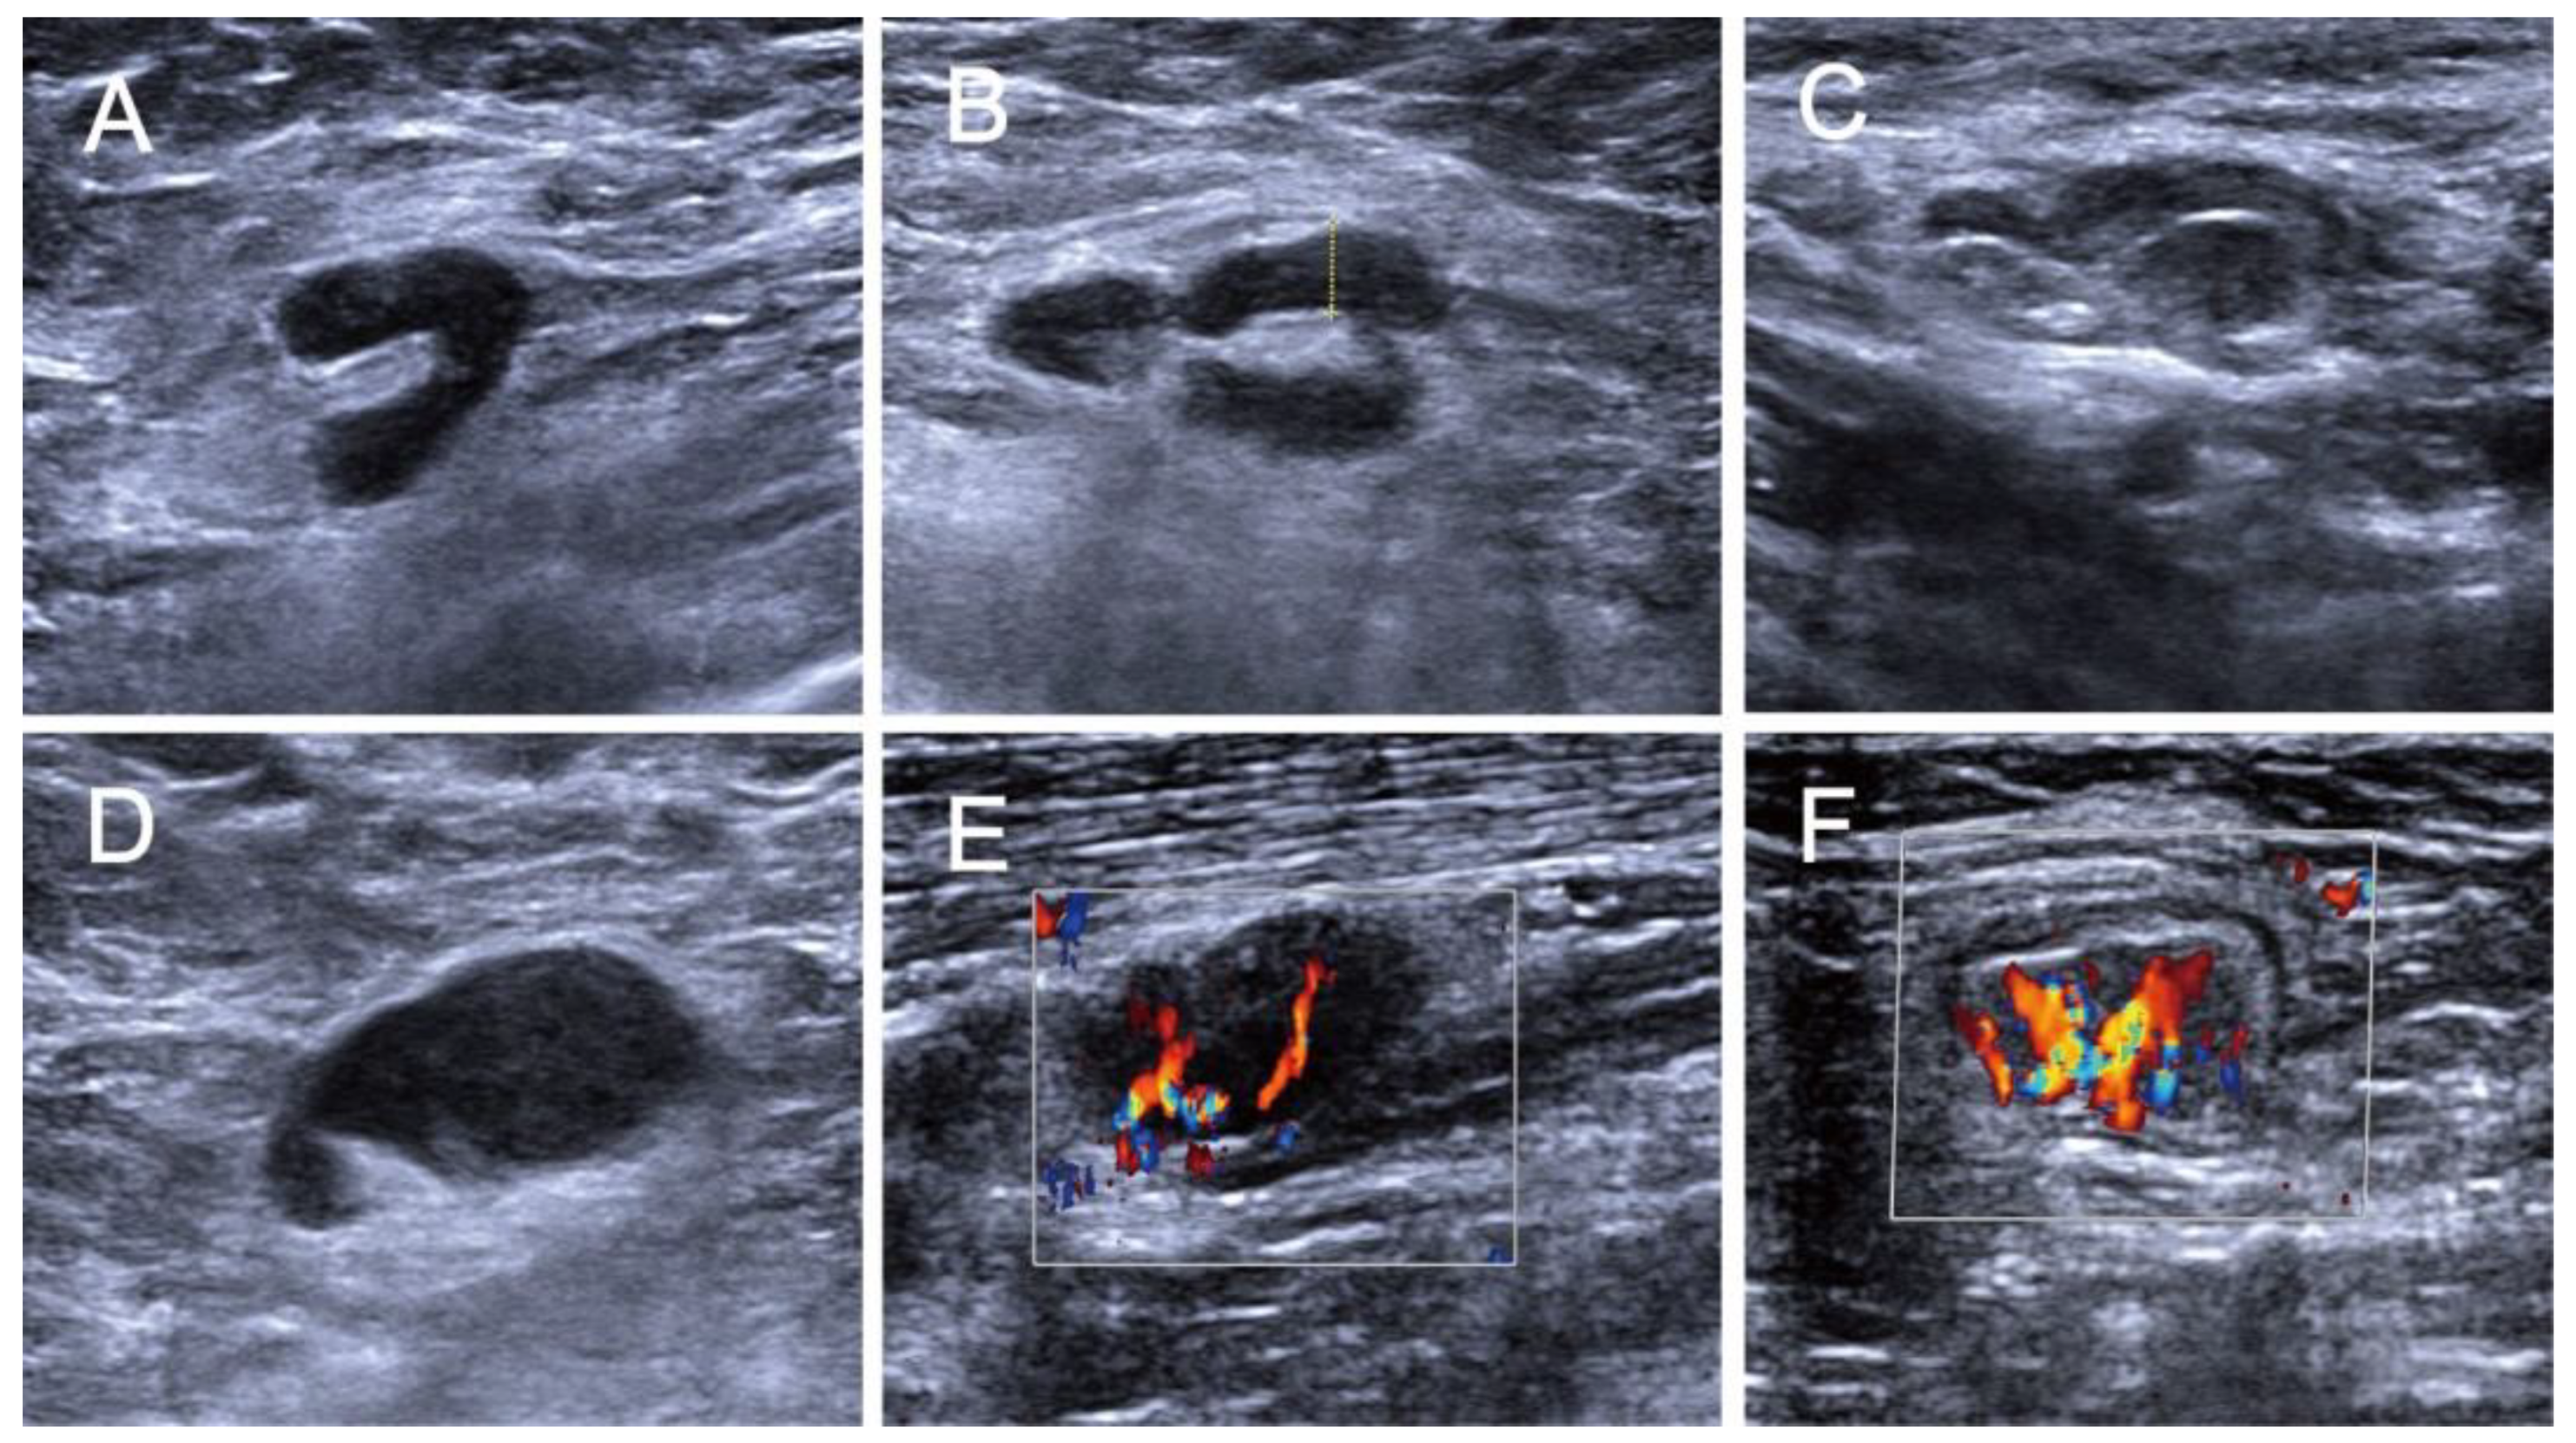

2.3. Ultrasound Examination